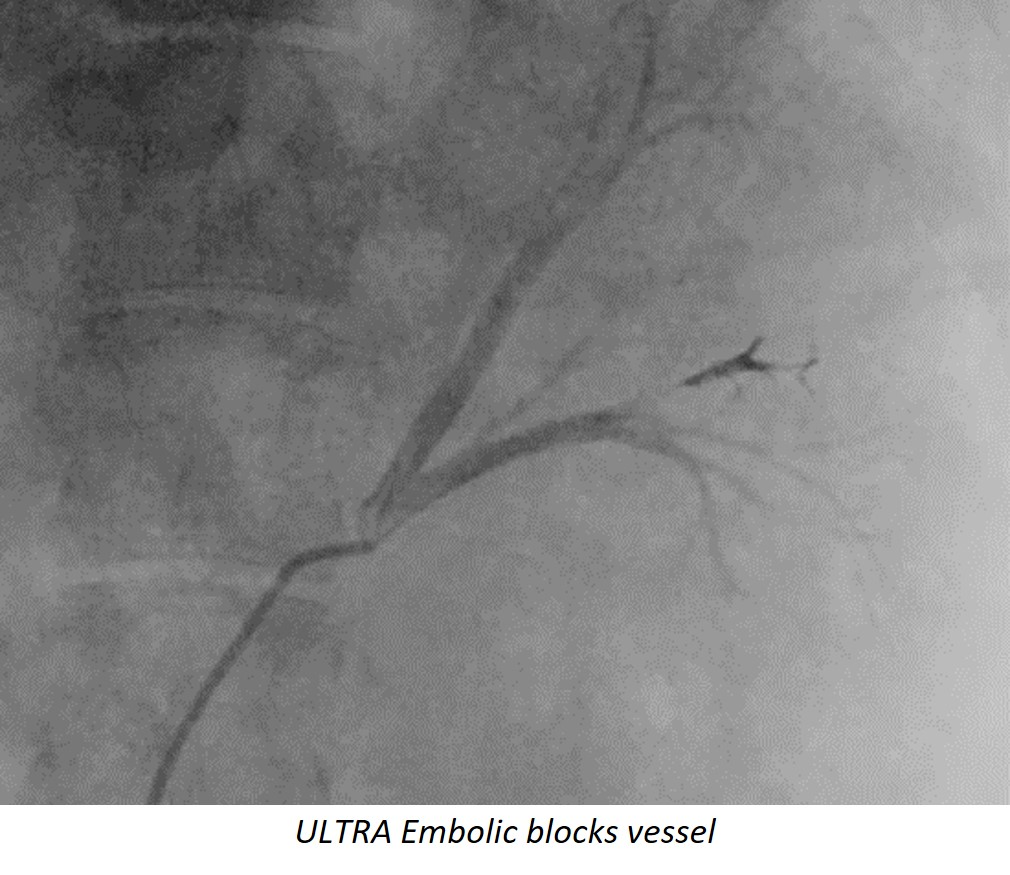

“We have seen a single delivery of ULTRA block a targeted vessel region quickly in an area that would usually require several coils,” noted Danny Smith, Vice President of Research & Development at Fluidx Medical. “ULTRA is visible under x-ray giving clinicians greater control and visualization of the embolic to ensure safe, accurate delivery.”